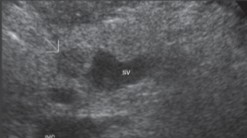

What does the white arrow point to?

Duct of wirsung

What does the white arrow point to?

Duct of wirsung